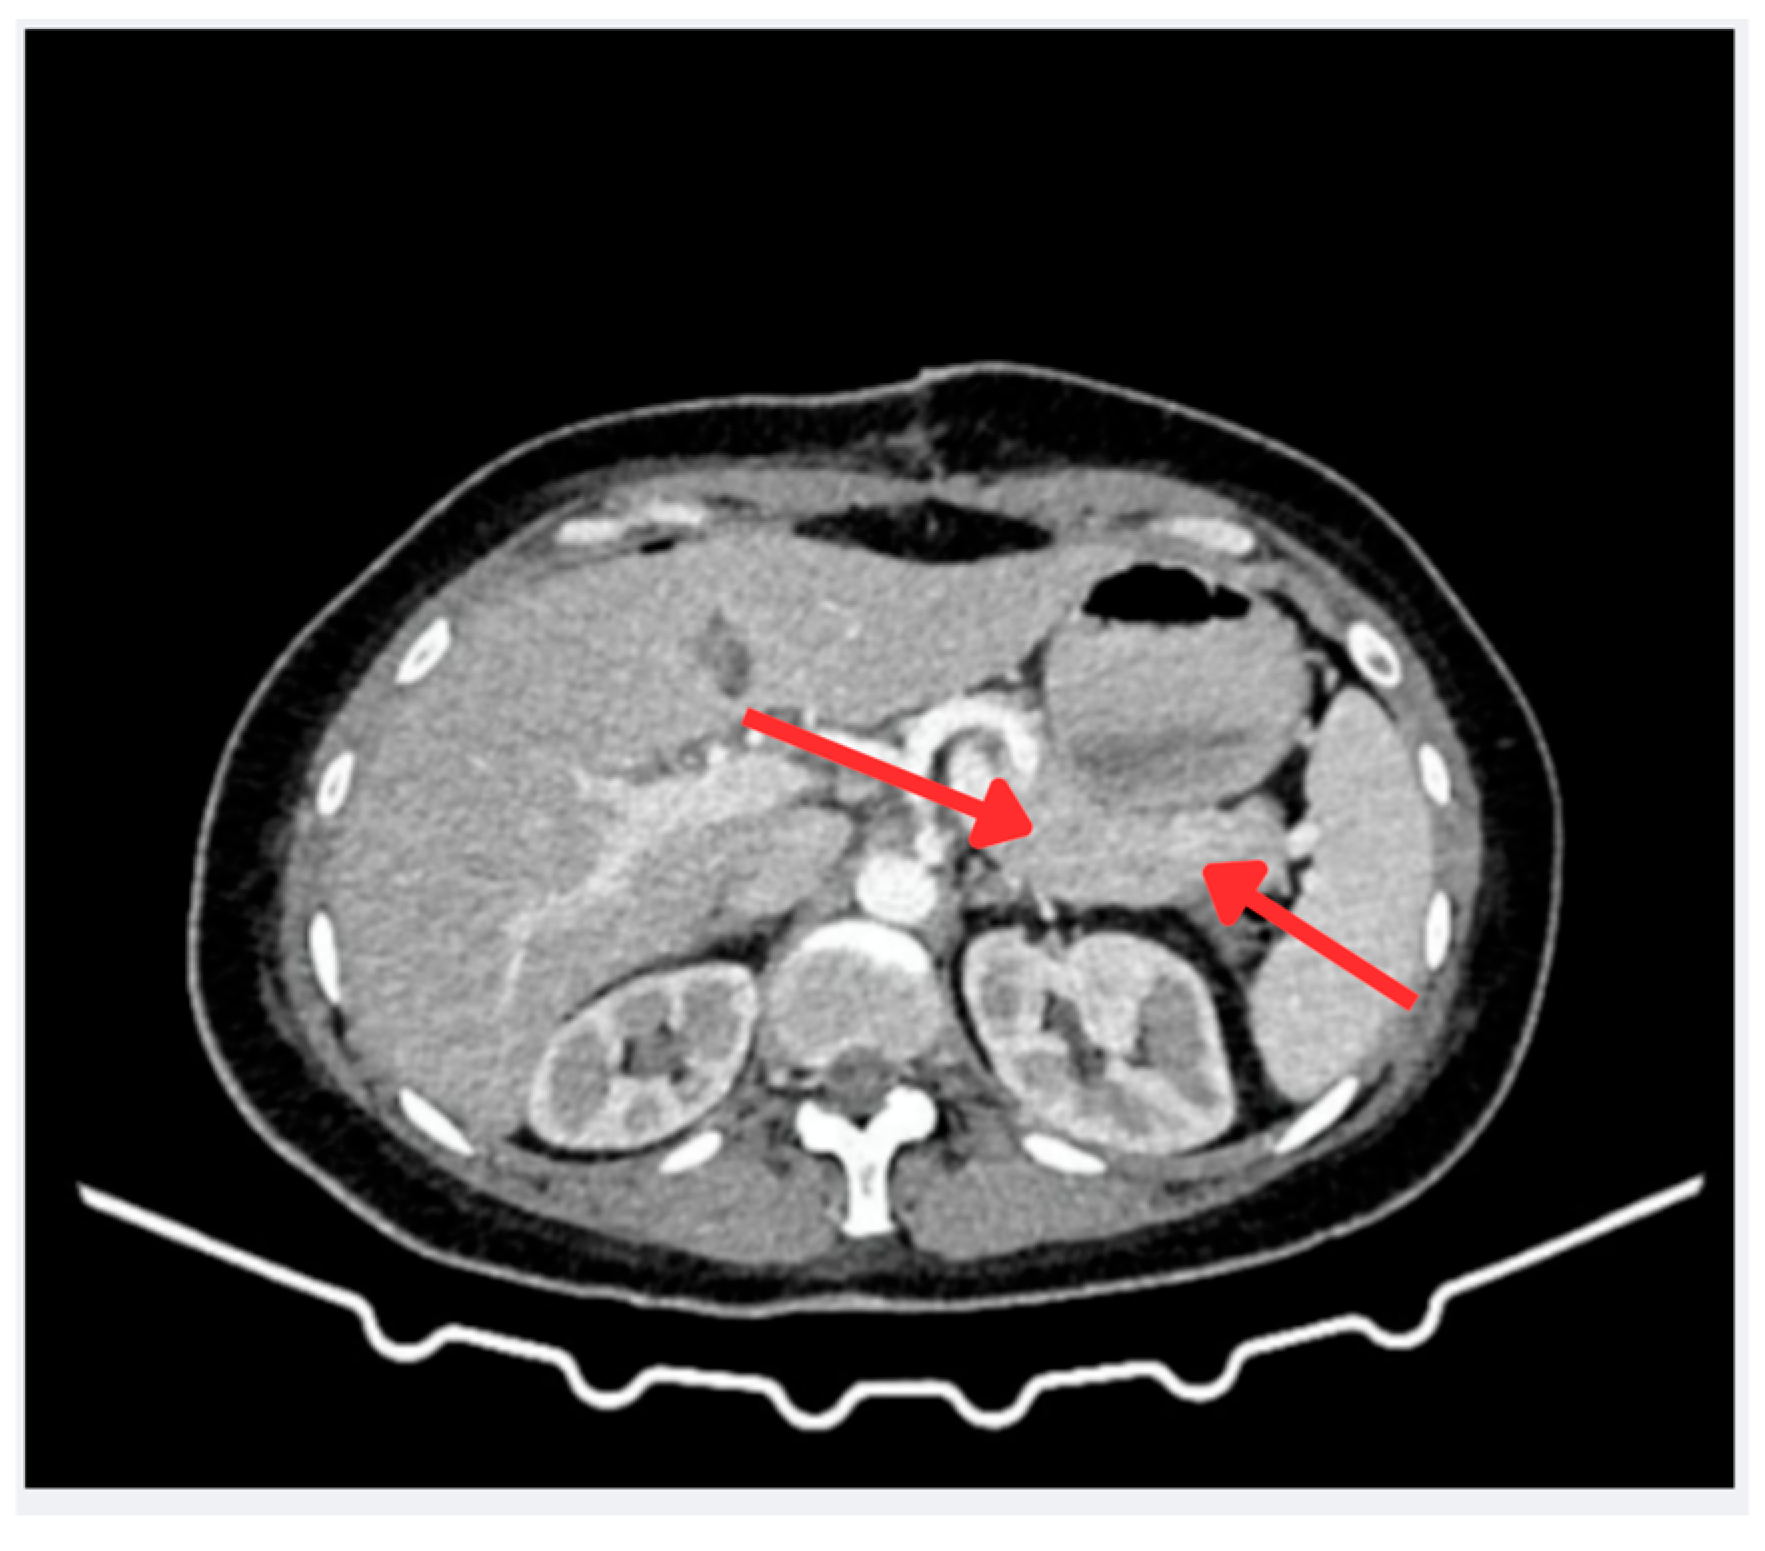

2.4. Surgical Intervention and Intraoperative Findings